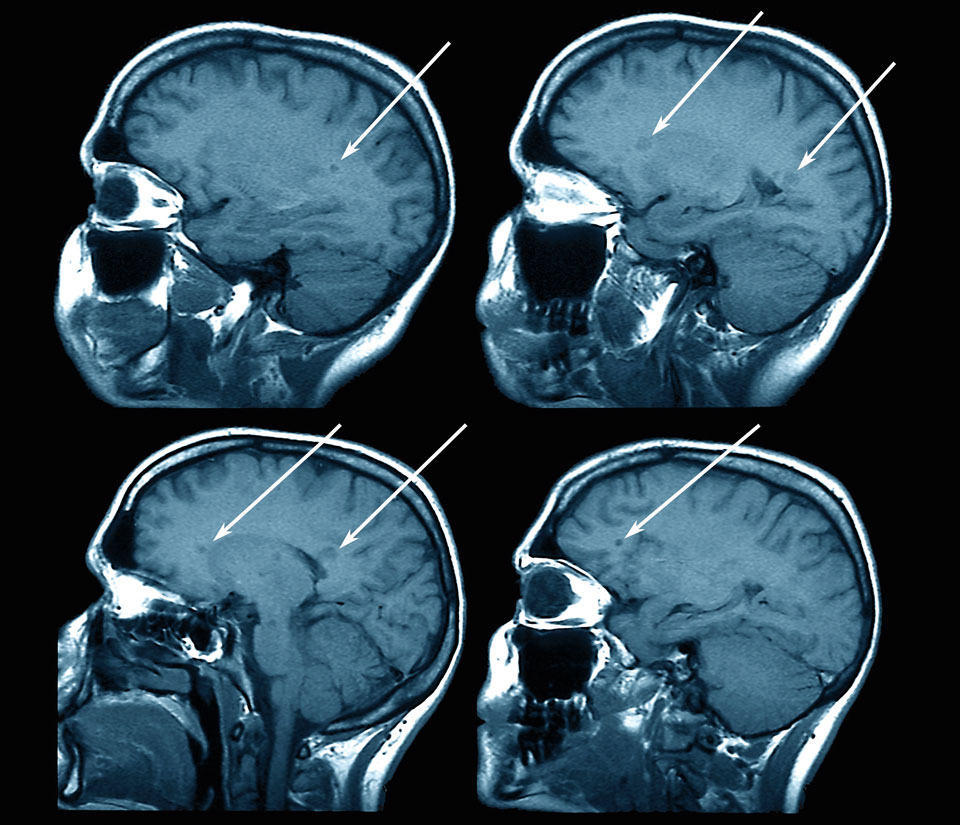

Im MRT wird die Multiple Sklerose sichtbar. Im MRT wird die Multiple Sklerose sichtbar. © Science Photo Library/Zephyr

Neue MRT-Marker bringen die MS-Diagnostik vo­ran. Vor allem beim Monitoring inflammatorischer und neurodegenerativer Prozesse gibt es Fortschritte. Doch nicht alles ist reif für die Routine.

Die Bildgebung hat dazu beigetragen, dass sich die pathogenetischen Vorstellungen von der Multiplen Sklerose radikal verändert haben, erklärte Professor Dr. Mike P. Wattjes, Institut für Neuroradiologie der Medizinischen Hochschule Hannover. So ist klar geworden, dass graue Substanz und Rückenmark für die Pathogenese von hoher Bedeutung sind. Insbesondere der spinale Befall hat sich als starker Prädiktor für Langzeitbehinderung erwiesen. Auch weiß man mittlerweile, dass sich Inflammation sogar außerhalb des Hirnparenchyms manifestiert, zum Beispiel in den Leptomeningen.1